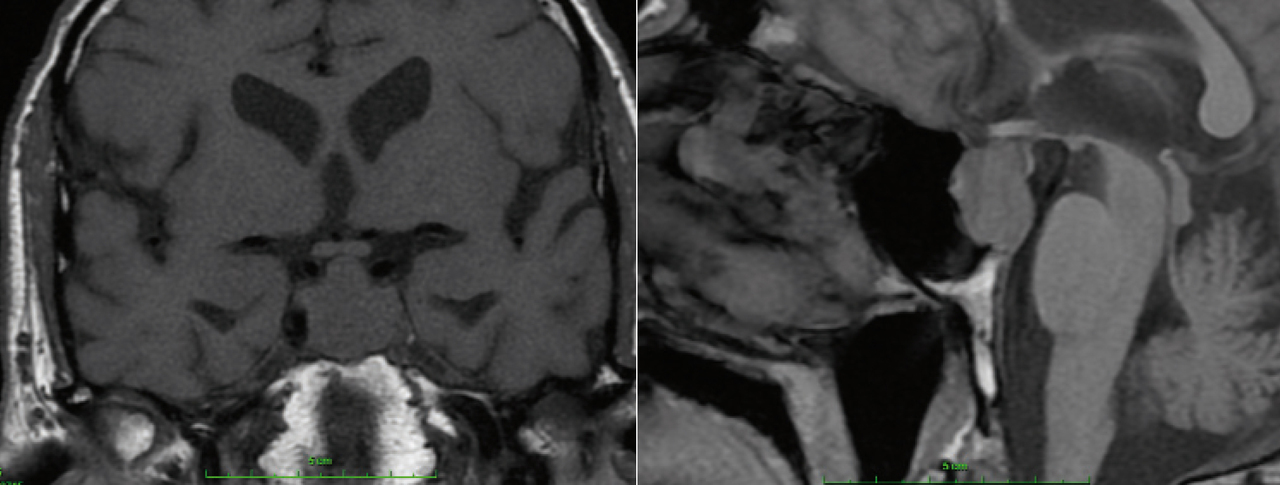

Quel est votre diagnostic ?

Il s'agit d'un macro-adénome hypophysaire mis en évidence sur une IRM, coupe coronale et sagittale T1. Les adénomes hypophysaires sont des tumeurs bénignes qui se développent au sein de l'antéhypophyse. Ils peuvent se révéler soit du fait de leur taille, soit du fait de leur caractère sécrétant. Il faut penser à ce diagnostic devant 3 types de syndromes : un syndrome tumoral en cas de macro-adénome (céphalées, troubles visuels) ; un syndrome d'hypersécrétion hormonale (hyperprolactinémie, acromégalie, hypercorticisme, exceptionnellement une hyperthyroïdie) ; et un syndrome d'insuffisance antéhypophysaire. Les macro-adénomes hypophysaires s'étendent en extrasellaire, leur signal est iso-T1, et souvent hétérogène en T2, les plages nécrotiques apparaissent en hypersignal T2. La prise de contraste est le plus souvent hétérogène.